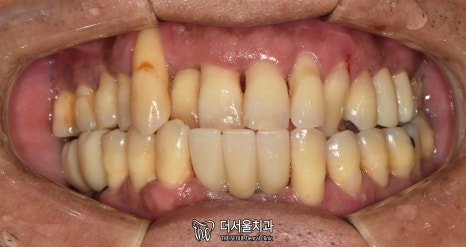

먼저 사진을 보겠습니다.

여러분이 보더라도

구강 상태가 심각하다는 걸 알 수 있습니다.

올바른 교합이 이뤄질 수 없을 뿐더러

치경부 마모증에 쌓여있는 치석에 충치까지

손댈 부분이 너무 많네요.

게다가 구취까지 나고 있었기에

걱정되는 상황이었습니다.